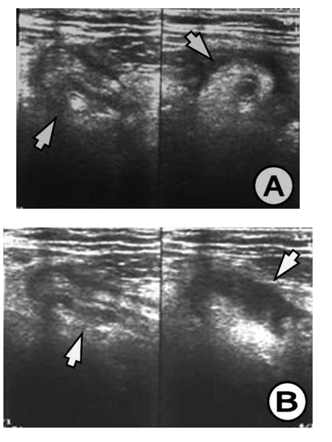

The appendix on US study is demonstrated by: hypo echoic lumen, hyper echoic mucosa, iso echoic lamina propria, hyper echoic submucosa, hypo echoic muskularis and hyper echoic serosa. The increased size of the appendix is a sign for phlegmonous or gangrenous appendicitis (Figure 1). The present appendicolith is demonstrated as hyper echoic mass that fills in the lumen and gives acoustic shadow (Figure 2B). When the appendicolith should be visualized, the wall thickness and the compressibility are not the features for making the diagnosis of acute appendicitis. The gangrenous appendicitis has changes in echogenity in all layers and the same are with the uniform echogenity and cannot be distinguished (Figure 3A). If the ill defined or hypo echoic mass is seen that surrounds the appendix that presents the periappendiceal inflammation (Figure 4). The ill defined appendiceal wall is suggestible, but not diagnostic for the periappendiceal process. The fluid presence into the appendiceal surrounding, with appendiceal wall echogenity changes is US feature for perforation (Figure 3B). The positive lymph nodes are oval hypo echoic and they don’t change the shape on compression.

Figure 2 (A) Appendix increased in size, thickened wall, widened lumen, US finding for appendiceal phlegmon, (B) Clearly visualized appendicolith into the lumen of the appendix, which is with thickened wall and widened lumen, US finding for appendiceal phlegmon.